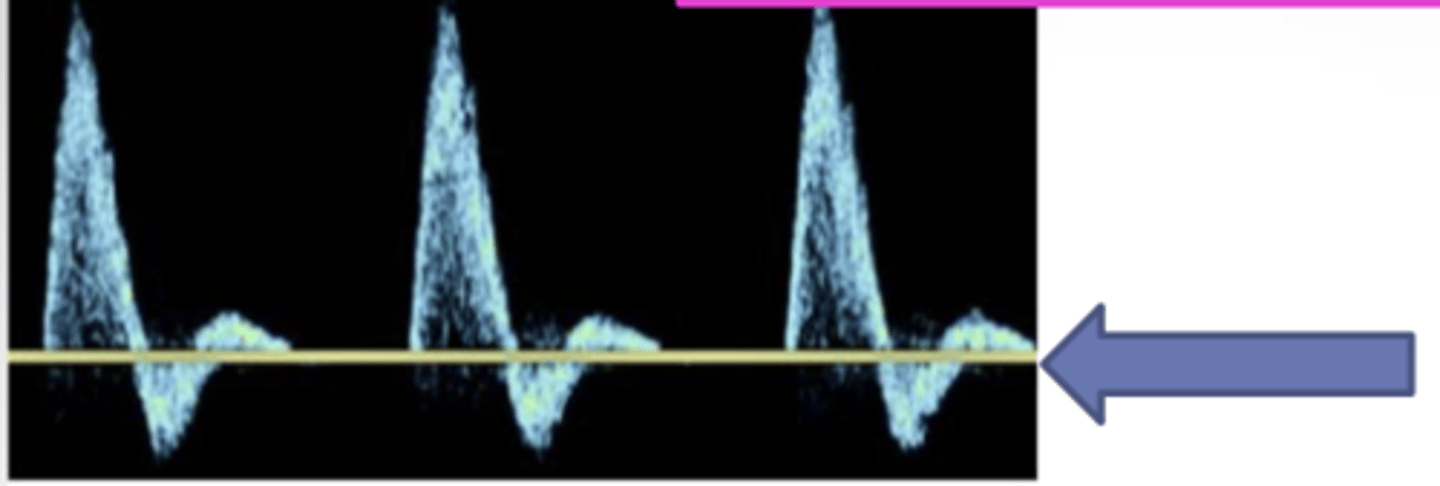

Turbulence

-forward and reversed (bidirectional) flow

-marked spectral broadening

-variable velocities

-post stenosis